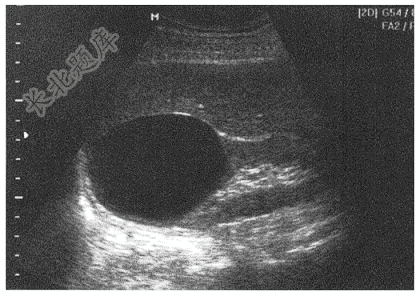

- 单项选择题女,35岁,时有腰部酸痛,体检超声如图,诊断为( )

A、肾错构瘤

B、肾脓肿

C、多囊肾

D、肾癌

E、肾囊肿